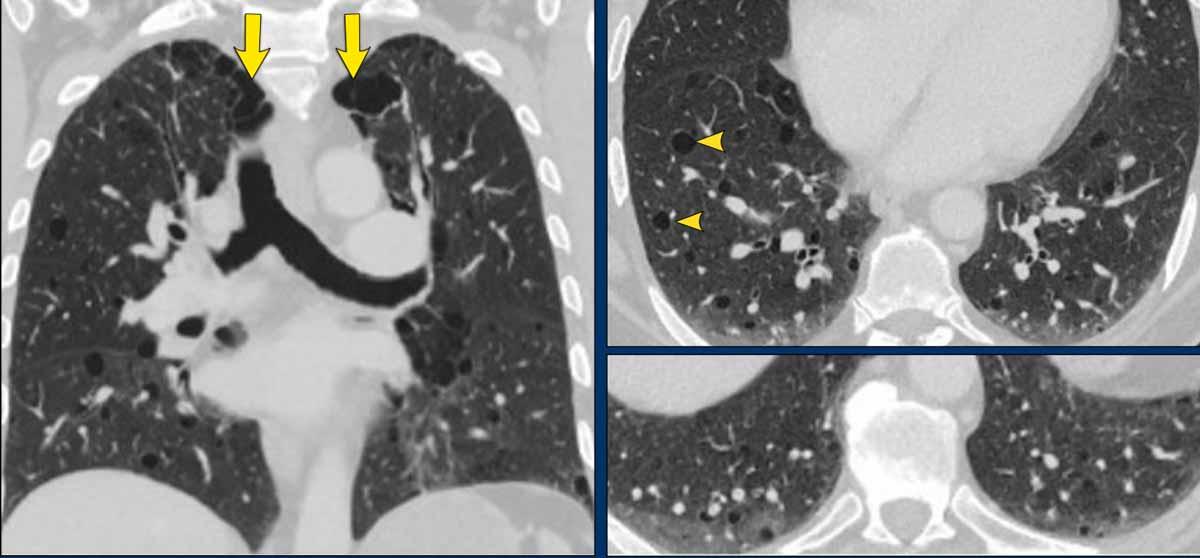

Hình ảnh

- Các nang BHD. Một số nang tiếp giáp với màng phổi (mũi tên vàng) hoặc các rãnh liên thùy. Các nang ở vùng phổi thấp cũng có thể gặp trong LIP. Khí phế thũng cạnh vách liên tiểu thùy có phân bố ưu thế ở vùng phổi trên.

- Phân bố ưu thế ở vùng phổi thấp và các nang hình tam giác (đầu mũi tên) trong BHD.

- Lưu ý hình ảnh rất tinh tế với phân bố ưu thế ở vùng phổi thấp.

- Các nang BHD điển hình

Đây là hình ảnh của một phụ nữ 56 tuổi, có tiền sử tràn khí màng phổi tái phát và hiện tại nhập viện lần này cũng vì tràn khí màng phổi (mũi tên).

Hãy phân tích hình ảnh.

Nhận xét hình ảnh

Có nhiều nang thành mỏng – hơn bốn nang. Lưu ý vị trí phân bố gần các rãnh liên thùy và ở ngoại vi phổi.

Kết luận

Đây là trường hợp hội chứng Birt-Hogg-Dubé (BHD).

Bàn luận

Hai bệnh phổi dạng nang thường biểu hiện bằng tràn khí màng phổi là LAM và BHD.

LAM biểu hiện là các nang đơn thuần, thành mỏng, hình tròn hoặc bầu dục, đều đặn với phân bố lan tỏa.

Vị trí ngoại vi và cạnh rãnh liên thùy của các nang BHD thường tạo ra các góc nhọn, khiến chúng có hình dạng thấu kính.

Khi các nang có hình ảnh đặc trưng này, chúng có độ đặc hiệu cực kỳ cao cho chẩn đoán hội chứng Birt-Hogg-Dubé.